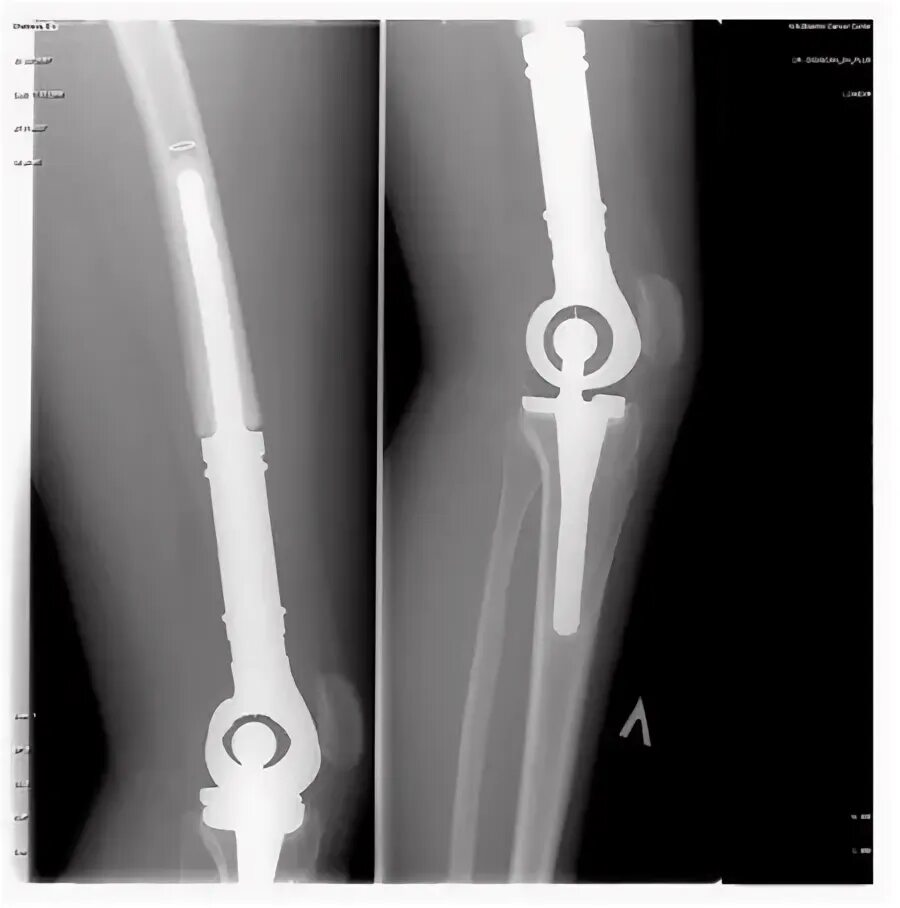

Можно ли мрт после эндопротезирования тазобедренного сустава